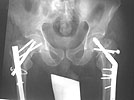

AP Pelvis

Lt femur

Rt femur

We decided to fix the Lt femur with a few lag screws on the proximal part andstabilize the femur with long Richard plate that was inserted in a sub-muscularfashion, in order to avoid opening the main shaft fx (the so-called biologicfixation - see Lt leg incisions.).

On the Rt side I replaced the recon nail with a longer one (accepting its toolateral and anterior entering point), I added a proximal locking screw (anterior toposterior) in the subtrochanteric region through a self-made extra hole, and two 6.5cancellous hip screws posterior to the nail.